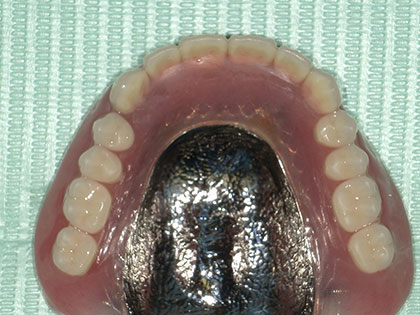

• 治療完了時の写真がこちら

• 義歯(入れ歯)治療完了時1

• 義歯(入れ歯)治療完了時2

• 義歯(入れ歯)治療完了時3

• 金属床義歯

• マグネットデンチャー(磁性義歯)

• 今回は上下に5か所ずつマグネットを装着し、その上に金属床義歯を上下にセットしました。

• 入れ歯の下に自分の歯があり、磁石が入ることにより入れ歯が食事の際に外れたり、沈み込みがなくなり、よく噛めるようになります。